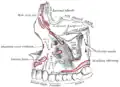

Superfície lateral.

Superfície lateral. -